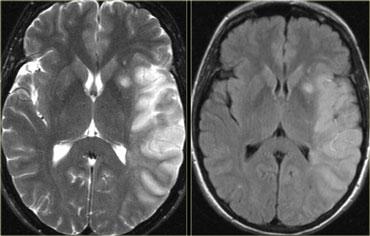

MRI

Trên chuỗi xung PD/T2W và FLAIR, nhồi máu não biểu hiện là vùng tăng tín hiệu.

Các chuỗi xung này phát hiện 80% nhồi máu não trước 24 giờ.

Chúng có thể âm tính trong vòng 2-4 giờ sau khởi phát!

Hình bên trái là chuỗi xung T2W và FLAIR cho thấy tăng tín hiệu trong vùng tưới máu của động mạch não giữa.

Lưu ý sự liên quan của nhân đậu và vỏ não đảo.

Tăng tín hiệu trên chuỗi xung MRI thông thường tương đương với giảm tỷ trọng trên CT.

Đây là kết quả của tổn thương không hồi phục với hoại tử tế bào.

Vì vậy, tăng tín hiệu có nghĩa là tiên lượng XẤU: não đã chết.